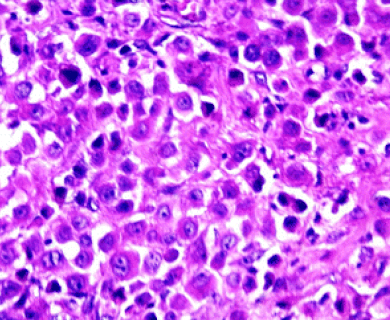

“Epithelioid” and “epithelial” are sometimes used in ways that feel interchangeable. But epithelial cells are normal cells that line the skin and the inside of organs. Epithelioid cells can be found in both cancerous and non-cancerous conditions. Epithelioid cells look like epithelial cells, which are shaped like columns or cubes. However, epithelioid cells may come from different types of cells that have mutated or changed shape, taking on an appearance similar to epithelial cells.

Epithelioid mesothelioma cells clump together in groups and don’t tend to travel. These cell types are less likely to spread to other areas of the body. When a pathologist confirms the presence of specific cancer cells, an accurate diagnosis of your mesothelioma type can be made.

The tool or technique for studying cancer tissues is called immunohistochemistry. Pathologists look at stained samples, testing for certain proteins linked to epithelial cells. If pathologists find proteins from other cancers, they’ll rule out epithelioid mesothelioma.

The proteins that help doctors identify epithelioid mesothelioma from different types of cancer include: calretinin, D2-40, keratin 5/6, podoplanin and WT-1 protein. An official diagnosis depends on more than just immunohistochemistry. It also considers the tumor’s appearance, location and cell traits.

While epithelioid is a subtype of mesothelioma, there are further subtypes of the epithelioid type. Pathologists can identify these cell subtypes with immunohistochemistry.

Solid

Well-differentiated solid cells group in nests, cords or sheets. They resemble noncancerous abnormal cell growth. Poorly differentiated cells may look like large cell carcinoma or lymphoma.